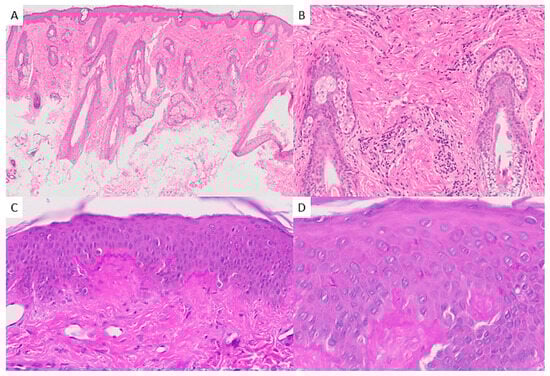

2.2. Histopathologic Findings

3.4. Histopathology